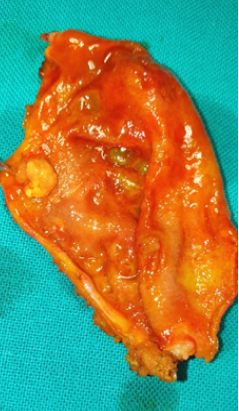

Η μέση ηλικία των ασθενών που εξετάστηκαν , ήταν 53.2 έτη ( 26 – 80 έτη ) Η σχέση Α:Θ ήταν 1:1 . Συνολικά 36/38 ασθενείς , είχαν συμπτώματα , τα οποία θα μπορούσαν να συσχετισθούν με νόσους της χοληδόχου κύστεως . Από αυτούς , 32/36 είχαν/εμφάνισαν άλγος στο δεξιό υποχόνδριο , που θα μπορούσε να χαρακτηριστεί κολικός των χοληφόρων και 2/36 είχαν συμπτωματολογία οξείας χολοκυστίτιδας . Ανάμεσα στους υπόλοιπους 4 ασθενείς , οι δύο εξετάστηκαν για άλγος στο υπογάστριο και ο ένας για την διερεύνηση υψηλού πυρετού στα πλαίσια της οποίας εντοπίστηκε τυχαία υπερηχογραφικά ο πολύποδας της χοληδόχου κύστεως . Τέλος , ένας ασθενής , εξετάστηκε για ίκτερο αγνώστου αιτιολογίας , χωρίς να εντοπιστούν υπερηχογραφικά σημαντικά ευρήματα στα χοληφόρα . Το μέγεθος της βλάβης , ήταν αξιοσημείωτο μόνο στους 18 από τους 38 ασθενείς . Από τους συνολικά 34 χειρουργηθέντες ασθενείς , μόλις 11 από αυτούς βρέθηκαν να έχουν ιστοπαθολογικά επιβεβαιωμένες/επαληθευμένες πολυποειδείς βλάβες .Από την ιστολογική εξέταση των αφαιρεθέντων /εκταμέντων χοληδόχων κύστεων , η μία ήταν φυσιολογική , 7 είχαν χοληστερινικούς πολύποδες , μία εμφάνιζε πολυποειδή χολοκυστίτιδα και δύο είχαν αληθή νεοπλάσματα χοληδόχου κύστεως . Ένας ασθενής είχε αδένωμα χοληδόχου κύστεως , ενώ ο άλλος αδενοκαρκίνωμα . Η συχνότητα εμφάνισης κακοήθειας , ήταν 2.94% , δηλαδή 1/34 . Όλοι οι ασθενείς με νεοπλαστικούς πολύποδες , είχαν μονήρη βλάβη > 1 εκ . σε διάμετρο , ενώ οι ασθενείς με μη-νεοπλαστικές βλάβες , είχαν πολλαπλές βλάβες < του 1 εκ . σε διάμετρο . Σε όλους τους χειρουργηθέντες ασθενείς , εκτός από ένα , ανευρέθησαν ιστοπαθολογικά , παθολογικές χοληδόχοι κύστεις . Αυτό υποδηλώνει , την παρουσία χρόνιας χολοκυστίτιδας , ακόμη και αν δεν υπήρχαν πολύποδες . Εικόνα 1 . Πολύποδας χοληδόχου κύστεως . ( Αρχείο κος Β . Πενόπουλος ) . Εικόνα 2 . Χειρουργικά παρασκευάσματα . Πολύποδες χοληδόχου κύστεως . (Αρχείο κος Β . Πενόπουλος) .